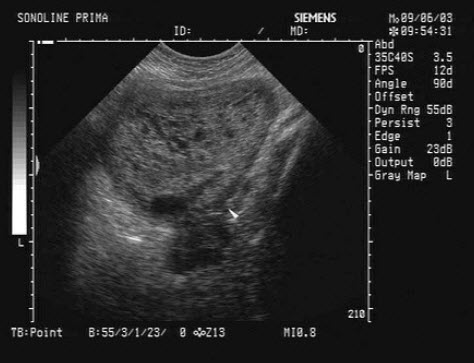

48、单项选择题

患者体检发现肝脏体积增大,超声见右叶巨大的强回声光团,边界见声晕,门脉见实质性光团充填,如图所示,考虑为()

A.肝癌并门脉癌栓

B.肝脓肿

C.肝囊肿

D.肝结核

E.肝血管瘤